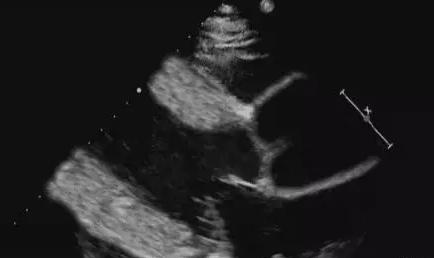

Points de diagnostic par ultrasons :

1. une longue histoire d'hypertension ;

2. épaississement uniforme du septum interventriculaire et de la paroi du ventricule gauche ;

3. hypertrophie du cœur gauche ;

4. diminution de l'amplitude du mouvement de la paroi du ventricule gauche ;

5) Insuffisance relative de fermeture de la valve mitrale.

Identification :

L'hypertrophie asymétrique du septum interventriculaire due à une maladie hypertensive se distingue de la cardiomyopathie hypertrophique principalement par ses antécédents, dans lesquels les échos du myocarde septal sont hétérogènes et grossièrement vitreux, mais surtout atypiques.

L'hypertrophie du cœur gauche et l'hypoplasie du cœur gauche causées par l'hypertension sont difficiles à distinguer de celles causées par la maladie coronarienne à l'échographie et doivent être associées à la coronarographie, aux antécédents et à d'autres informations cliniques ; les principes du traitement clinique sont fondamentalement les mêmes, de sorte que le diagnostic échographique de l'hypertrophie du cœur gauche et de l'hypoplasie du cœur gauche est suffisant.